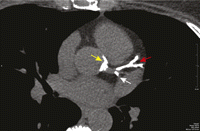

Single axial slice of the coronary calcium scan from the patient described in Clinical Case 1 (Box 1) that shows severe calcification of the left anterior descending coronary artery (red arrow), the portion of the circumflex coronary artery within the imaging plane (white arrow), and the aortic root around the origin of the left main coronary artery (yellow arrow).